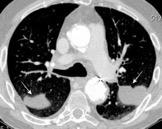

Signos radiológicos TC

Hallifax RJ et al. State-of-the-art: Radiological investigation of pleural disease Respiratory Medicine 2017

Nivel hidroaéreo o burbujas

Forma lenticular o elíptica Ángulos obtusos

> Grasa Extrapleural (60-80%)

Situación no gravitacional (no siempre)

Compresión de estructuras pulmonares

Límite muy bien definido Tabicación

Patrón ecográfico de empiema

Empiema

El derrame paraneumónico se convierte en complicado en 5-10% de los casos

Engrosamiento de la pleura parietal 36/ 59 exudados (61%) 56% de D. paraneumónicos 100% de empiemas Especificidad.. 96%.

Exudado versus trasudado.

Aquino SL, et al. Pleural exudates and transudates: diagnosis with contrast-enhanced CT. Radiology 1994